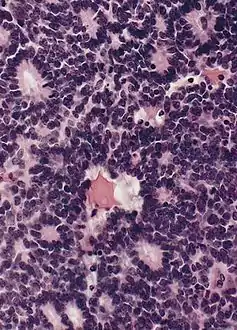

Micrograph of pineocytomatous/neurocytic pseudorosettes

Micrograph of pineocytomatous/neurocytic pseudorosettes Structure of pineocytomatous/neurocytic pseudorosettes

Pineocytomatous/neurocytic pseudorosettes

Histologic features of these two tumors are virtually identical, including their tendency to form neuropilrich rosettes, referred to as pineocytomatous/neurocytic rosettes in central neurocytoma. Both are quite similar to the Homer Wright rosette, but they are generally larger and more irregular in contour. The cells of the pineocytomatous/neurocytic rosettes are also considered to be much more differentiated than the cells forming Homer Wright rosettes in that the nuclei are slightly larger, more rounded, much less mitotically active, and paler or less hyperchromatic. In rare cases, these rosettes may aggregate in a sheet of back-to-back clusters resembling field stone pavement.[2]